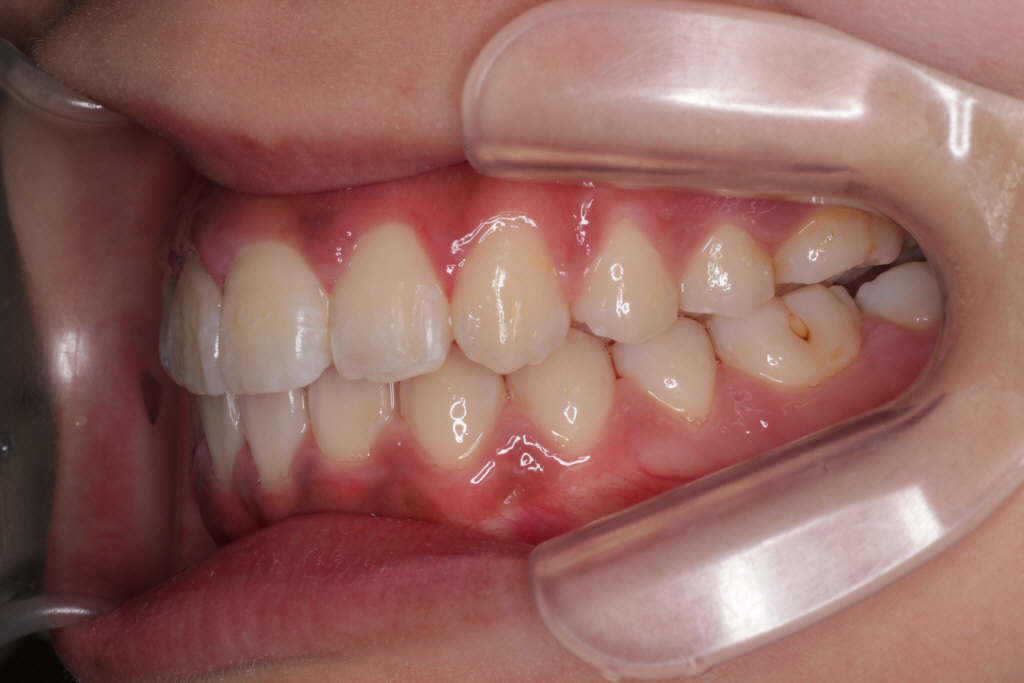

上下マウスピースを37枚最後まで1週間ずつ使い、6ヶ月後のお口の中の状態です。↓

① 左上の2番目の歯が歯列に入っていない

② 右上の2番目の歯が切端咬合と言って上下の歯の先端がぶつかっています。

③ 側方の上下の咬合関係が理想の上1本に対して下2本にはなっていません。

④ 左右の2番目、3番目あたりの噛み合わせがあまく、隙間がある。

このような症状を改善させるために、リファイメント2回目を行いました。